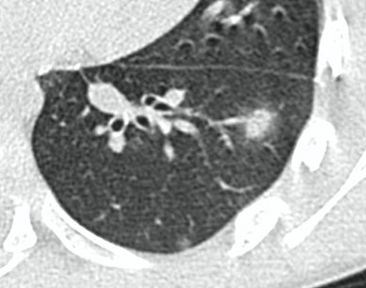

КТ имеет высокую чувствительность в выявлении изменений в легких, характерных для COVID-19. Применение КТ целесообразно для первичной оценки состояния ОГК у пациентов с тяжелыми прогрессирующими формами заболевания, а также для дифференциальной диагностики выявленных изменений и оценки динамики процесса. КТ позволяет выявить характерные изменения в легких у пациентов с COVID-19 еще до появления положительных лабораторных тестов на инфекцию с помощью МАНК. В то же время, КТ выявляет изменения легких у значительного числа пациентов с бессимптомной и легкой формами заболевания, которым не требуется госпитализация. Результаты КТ в этих случаях не влияют на тактику лечения и прогноз заболевания при наличии лабораторного подтверждения COVID-19. Поэтому массовое применение КТ для скрининга асимптомных и легких форм болезни не рекомендуется.

3. Применение лучевых методов у пациентов с симптомами ОРВИ легкой степени тяжести и стабильном состоянии пациента, возможно только по конкретным клиническим показаниям, в том числе при наличии факторов риска, при условии достаточных технических и организационных возможностей. Методом выбора в этом случае является КТ легких по стандартному протоколу без внутривенного контрастирования или РГ при ограниченной доступности КТ. Использование УЗИ в этих случаях нецелесообразно. Применение КТ исследования в сроки ранее 3 - 5 дней с момента появления симптомов заболевания является нецелесообразным.

15. Рекомендации по формированию описаний и оценке изменений в легких и ОГК при имеющейся/подозреваемой пневмонии COVID-19 представлены в Приложении 1.